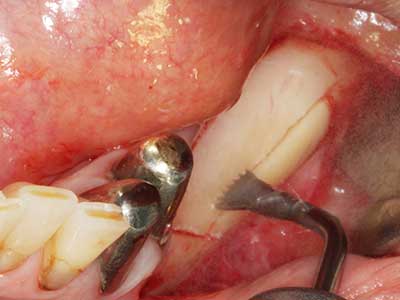

Fig. 3: Basal separation of the block is easier with specially angled attachments.

Fig. 4: Additional autologous bone chips are harvested with the bone scaler.

Fig. 5: Checking the block size at the recipient site.